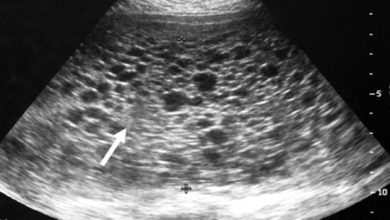

Mol Gebelik; Üzüm Gebeliği

Mol gebelik plasentanın anormal bir durumu. Nadir rastlanan bir hastalık olup 1000 de 1 oranında görülür. Mol gebelik halk arasında…

Üzüm Gebeliği-Mol Gebelik

Molar Gebelik nedir? Molar gebelik plasenta dediğimiz bebeğin anne rahmine yapışan eşinde görülen bir anormalliktir.Bu hastalıkta bebeğin anneye yapışan villi…